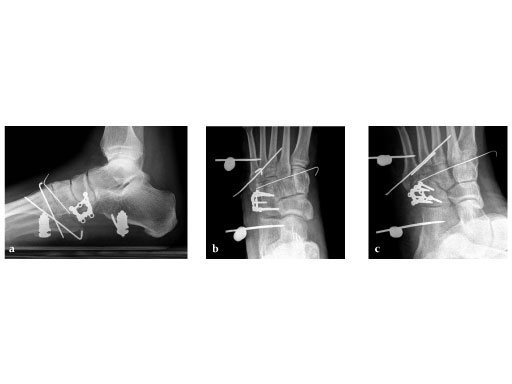

Case provided by Andrew K Sands, New York, US